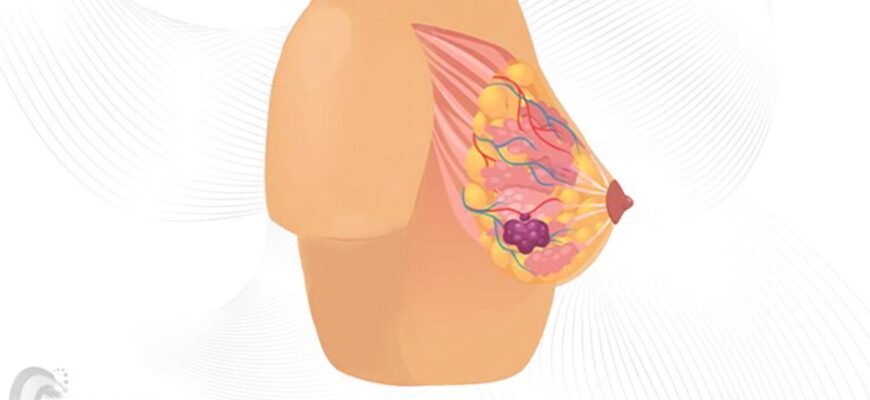

Фіброзно-кістозні зміни молочних залоз: що потрібно знати? Фіброзно-кістозні зміни молочних залоз — це не вирок, а частина життя багатьох жінок.

Фіброзні зміни в грудях: що вони означають? Фіброзні зміни в грудях — це щось, про що не так часто говорять у щоденних розмовах. Проте, коли стикаєшся